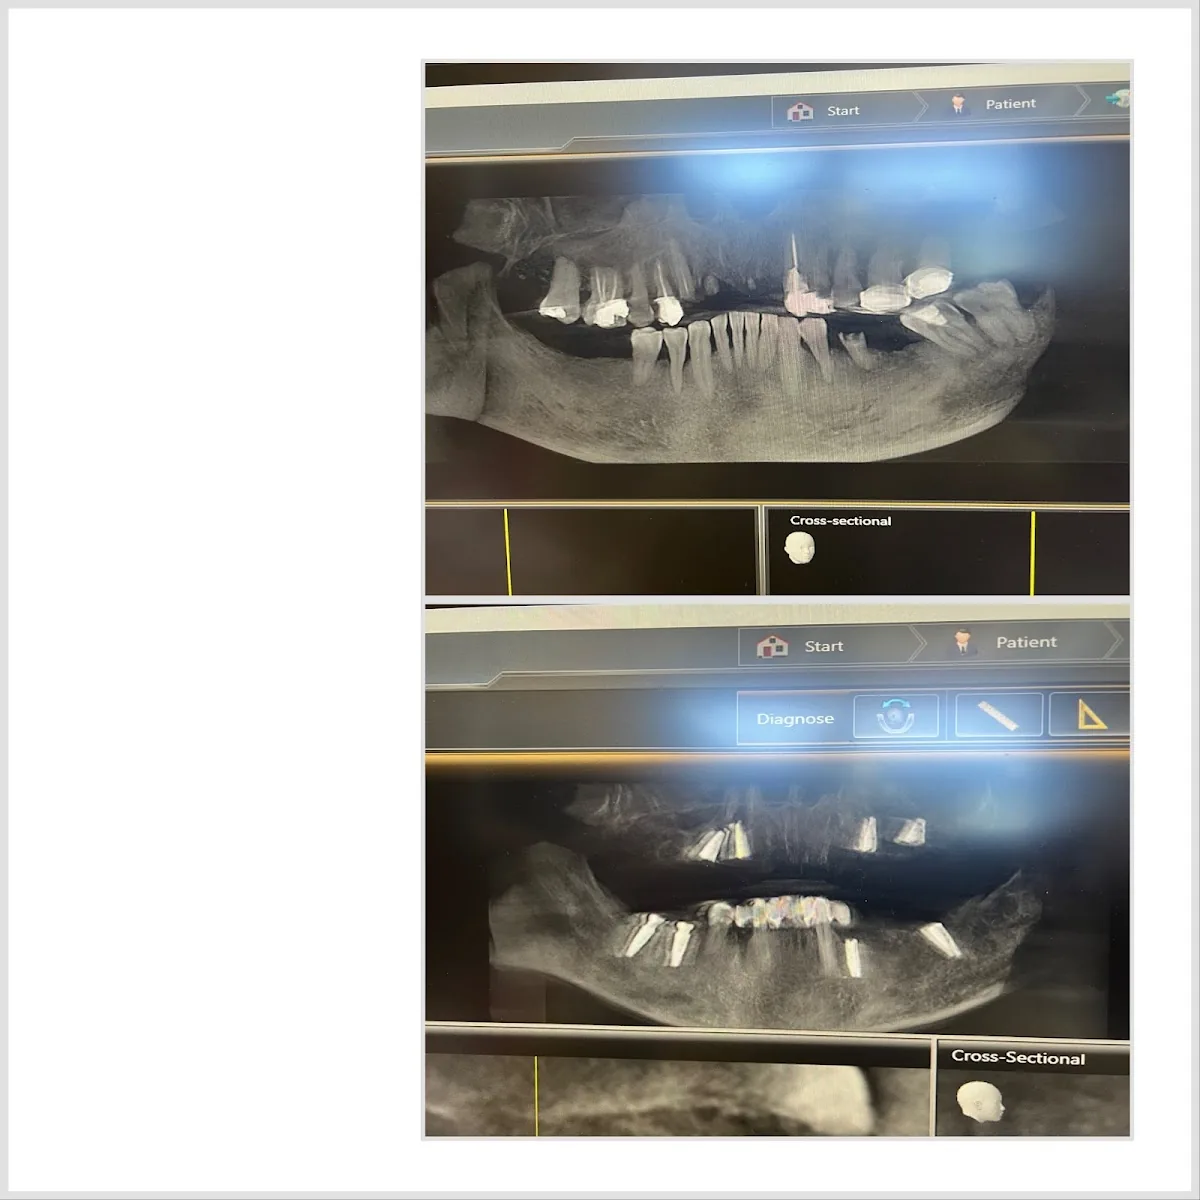

You can have a single missing tooth replaced with an implant here, or move to a full-arch restoration when multiple teeth are failing. Bone grafting and oral surgery are handled in-house, which keeps the treatment timeline tight when imaging shows pre-implant structural work is needed. Full mouth rehabilitation is the relevant option when older dental work has accumulated past the point where individual fixes deliver a stable, comfortable bite anymore, and the answer is a coordinated implant-and-prosthetic plan across the whole mouth.

If your implant case involves significant gum work or you've heard about laser-assisted periodontal-and-implant approaches and want to understand what that actually delivers, this is the kind of practice positioned around that exact specialty.